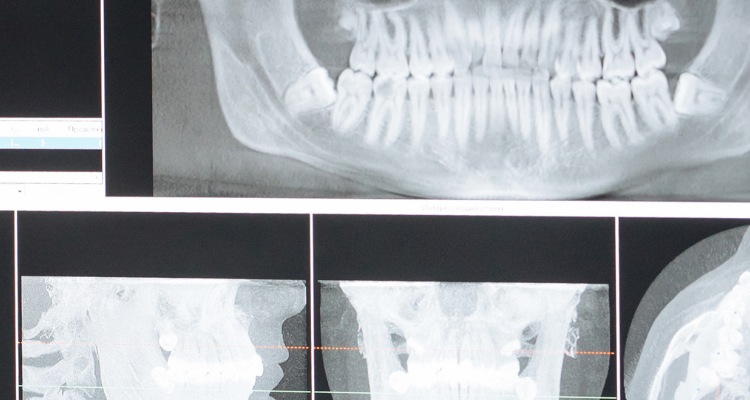

Your jawbone is maintained by use just as your muscles are maintained by exercise. Your teeth are anchored in supporting bone, and as you bite and chew, they stimulate your jawbone to keep it strong and healthy. Missing teeth means that the bone in that area no longer receives this stimulation, and over time, it will resorb, or deteriorate, and gradually cause a loss of stability and function for your remaining teeth.